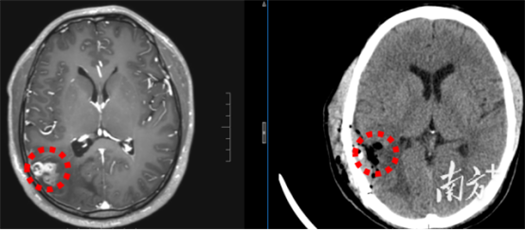

该院神经外八科二区副主任陈俊喜和主治医师王艮波接诊后,对比患者历次头部影像发现,病灶不仅位置移动,还呈现“隧道征”,高度指向脑裂头蚴病。后续血清检查结果也提示裂头蚴抗体阳性。

“除近期的癫痫大发作,患者此前频繁出现视野闪光、画面感,也是癫痫发作引起的。”陈俊喜解释,从影像来看,虫体已从大脑深部爬至表层,正是手术取出的好时机。很快,他带领团队为患者进行裂头蚴捉取手术,成功取出一条长约18cm的活虫。